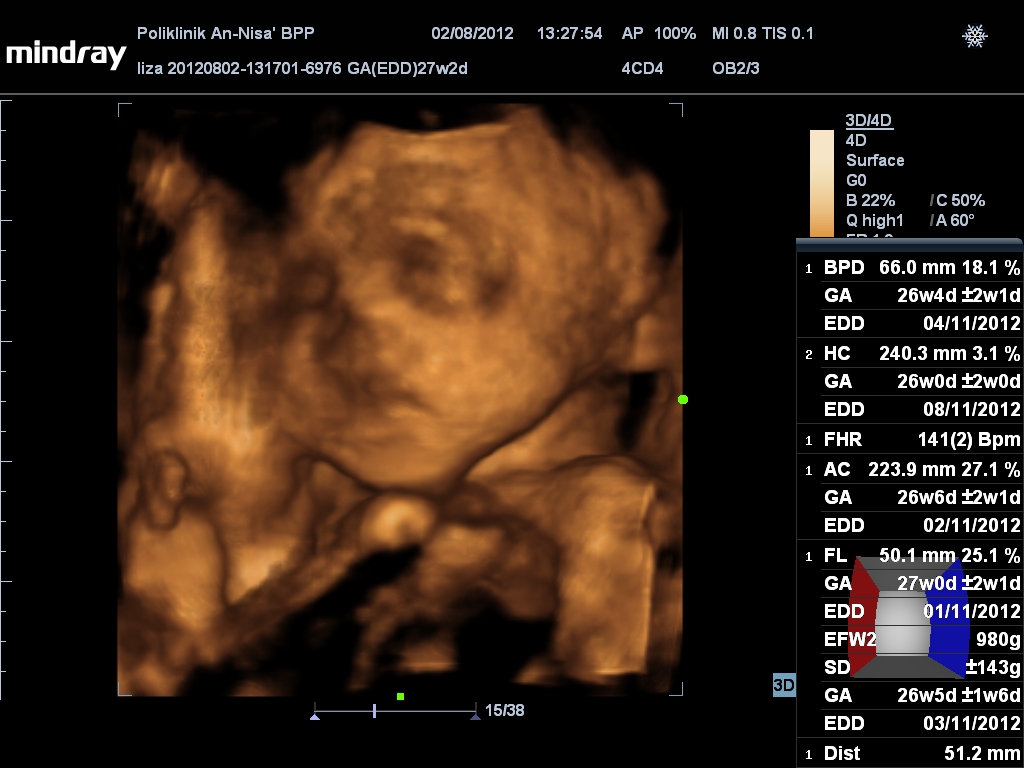

Si kecik dalam perut ni pun semakin aktif..ble malam lagi la menjadi..sampai senak2 perut ibu dia..nak kata lelaki..ble scan dah terang2 perempuan..alahai..dalam perut lagi ko dah lasak nak...ape lagi ble dah kuar nanti...makin menjadi ler ble dah join kakak2 yg tersangat ler gedik saat ni..kedua-dua kakak awak makin gedik dan cengeng...huhu...sabar je la...